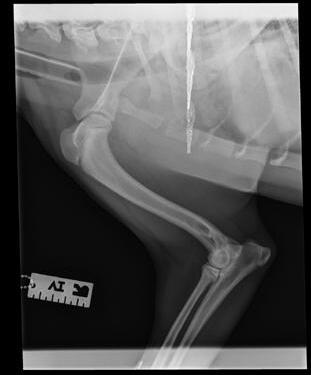

An 8-month-old female desexed Labrador retriever cross presented for a 4–6-week duration of left forelimb lameness.

On clinical exam, there was mild pain on manipulation of both shoulder joints.

Q. What is your radiological diagnosis?